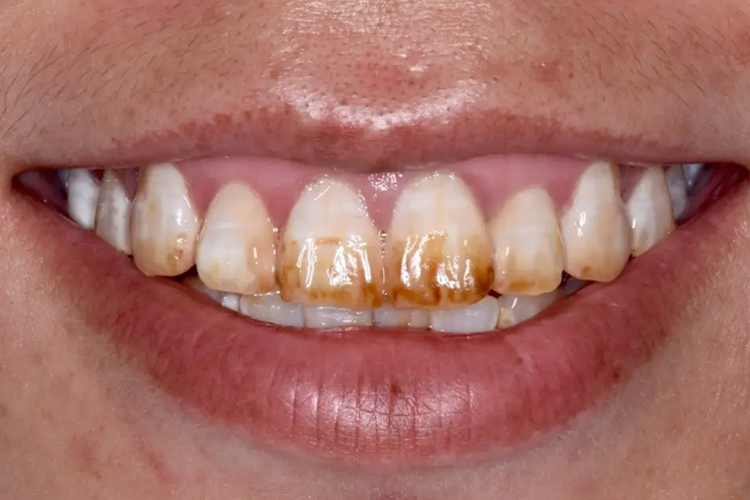

氟牙症

氟牙症恒牙多发,会出现对称性斑块或牙体缺损,还可在牙釉质上有白垩色或褐色的斑块以及缺损,形似牙齿上有一条一条的黄线,牙对摩擦的耐受性降低,但对酸的抵抗力增强。

四环素牙

四环素牙初期呈黄色,在阳光下呈现明亮的黄色荧光,逐渐由黄色变成棕褐色,可伴随一条条的黄线。